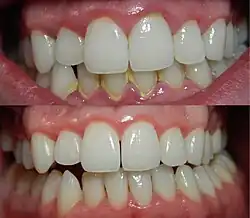

.jpg)

The signs and symptoms of gingivitis include:

- Swollen gums

- Bright red gums

- Gums that are tender or painful to the touch

- Bleeding gums or bleeding after brushing and/or flossing

- Bad breath (halitosis)

Additionally, the stippling that normally exists in the gum tissue will often disappear, and the gums may appear shiny as the gum tissue becomes swollen and stretched over the inflamed underlying connective tissue. The gingiva may become ulcerated and the gums may bleed with even gentle probing or brushing, and especially when flossing.